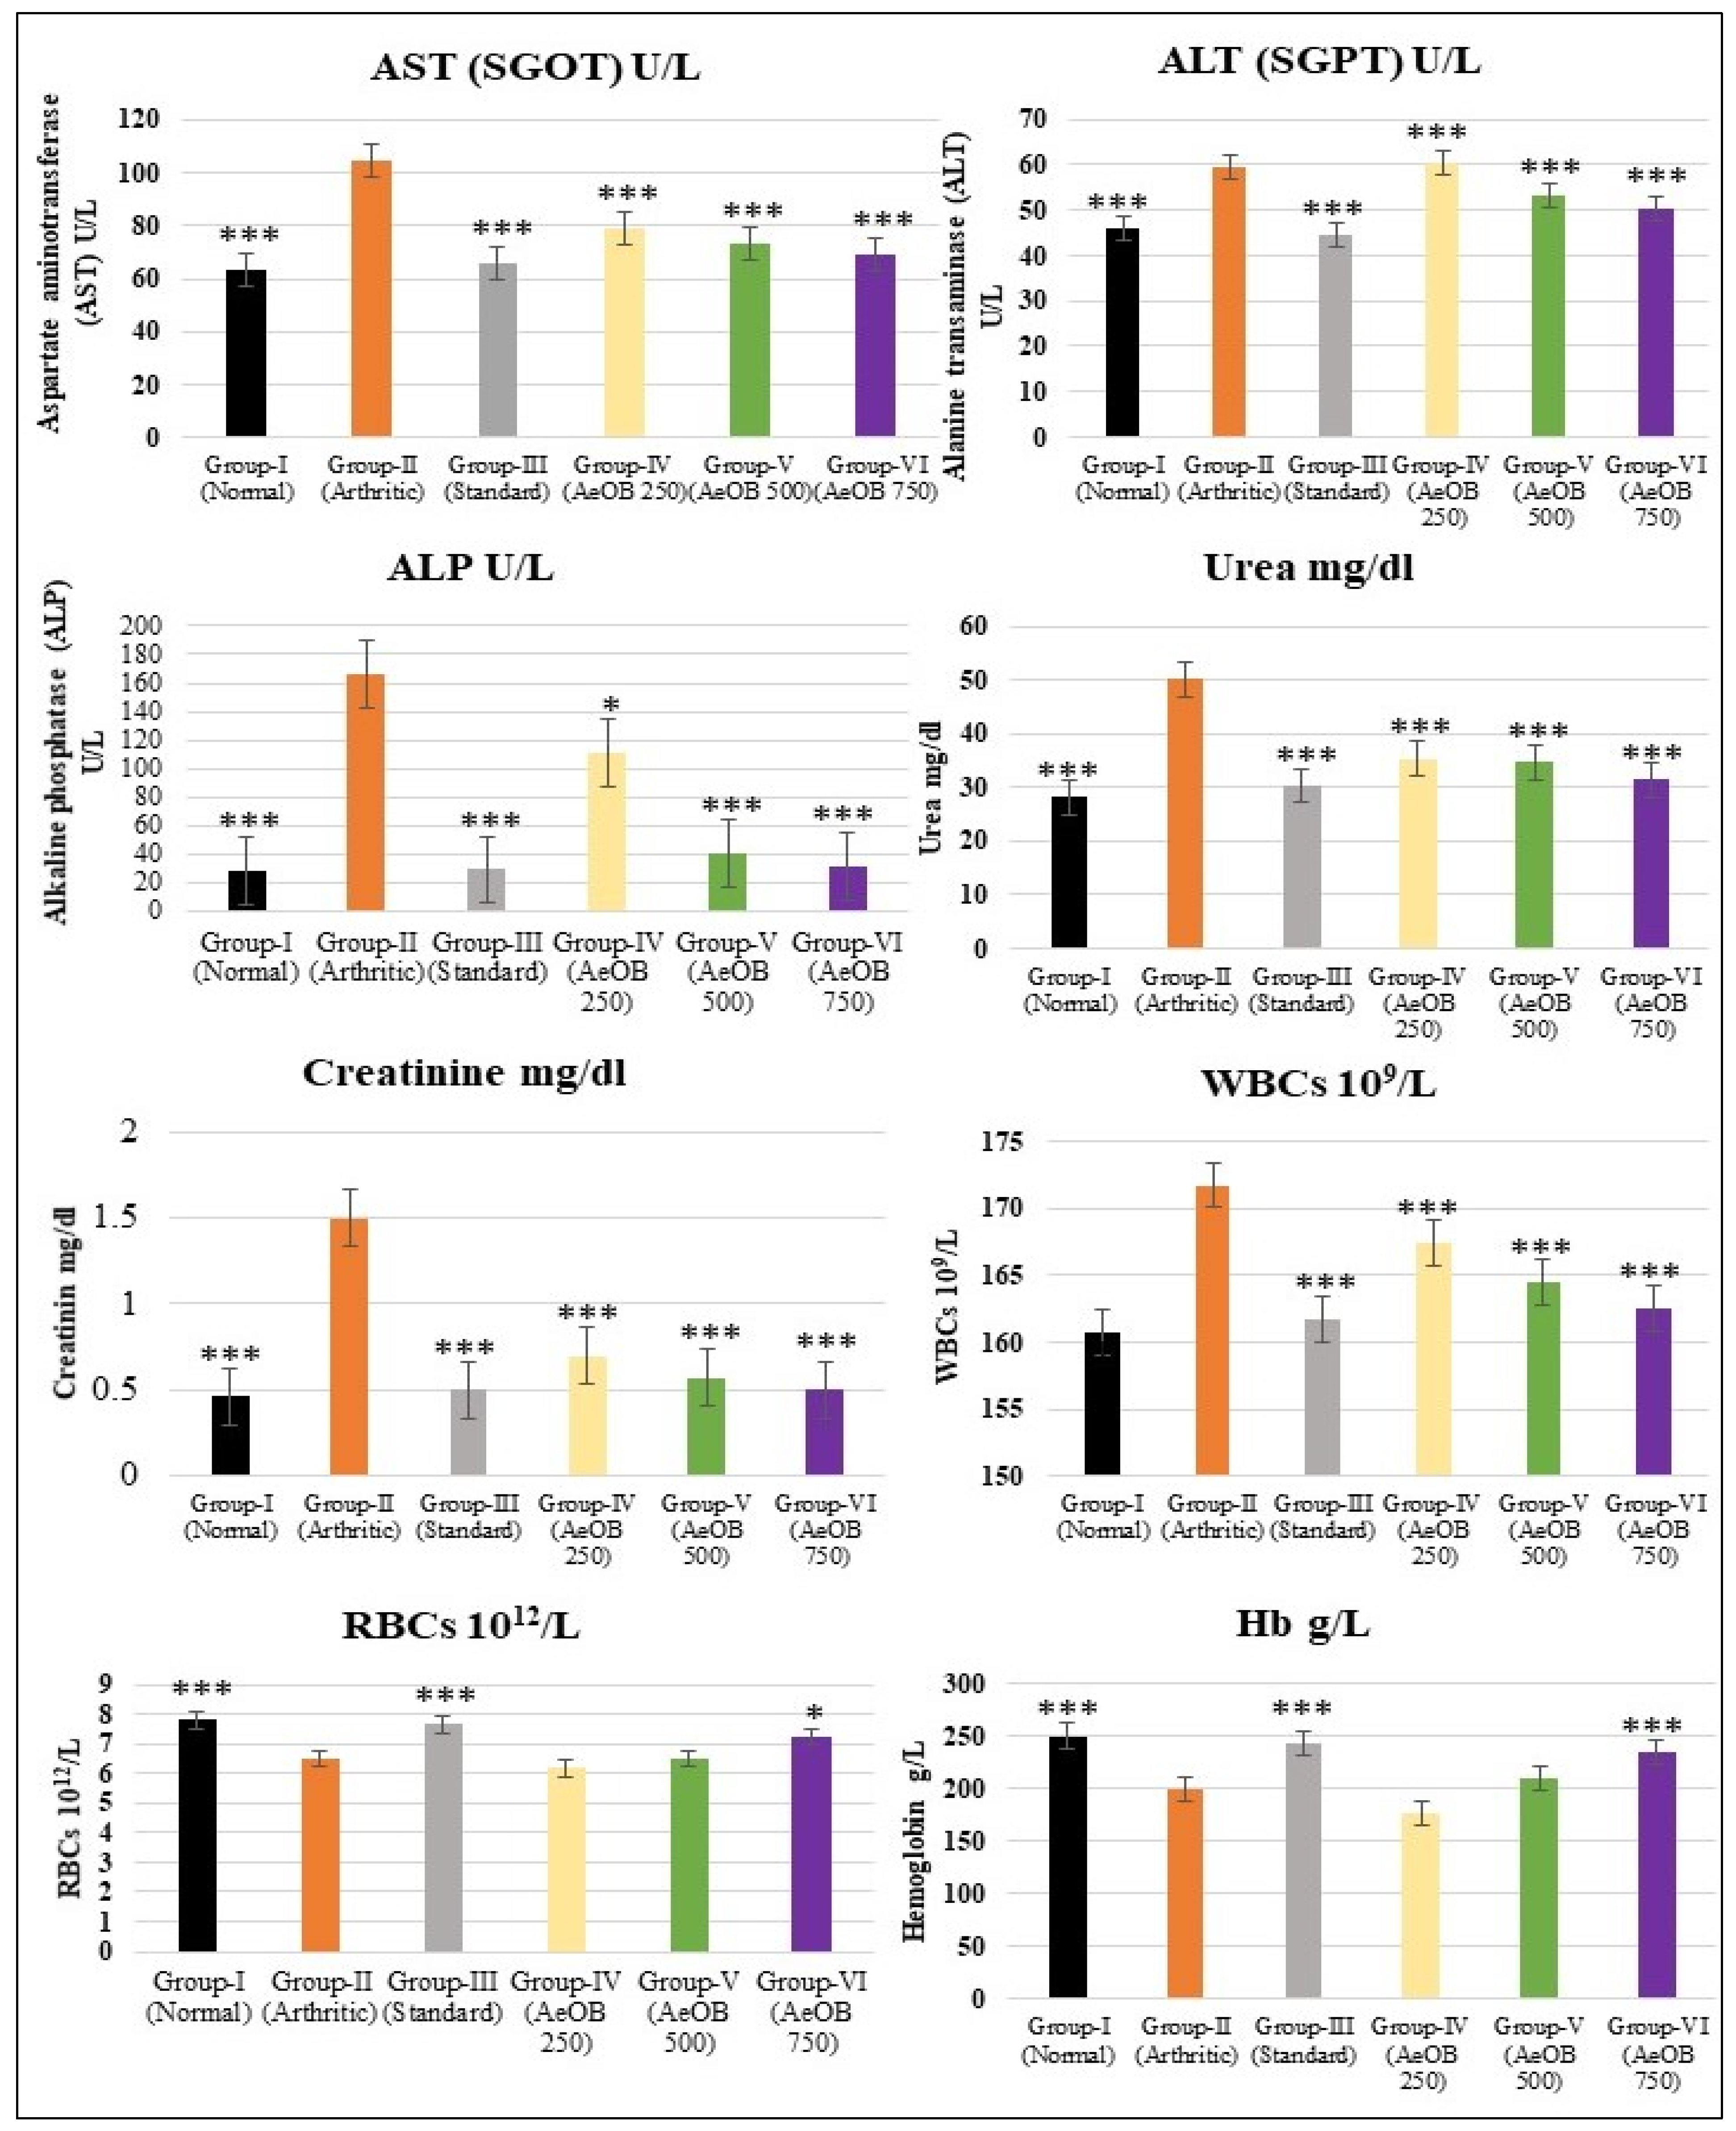

2.6.6. Hematological and Biochemical Estimation

4.7.11. Biochemical and Hematological Estimation